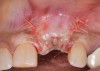

It is important to point out that not all implants presenting with mucogingival or esthetic complications require explantation, especially when the affected implants are partially supporting a multiple-unit restoration. This can be demonstrated in the following case. Implants were placed almost 20 years prior to the patient presenting with advanced soft-tissue recession on the maxillary right arch (Figure 15). There was a lack of keratinized/attached mucosa and buccal bone deficiency. This bone deficiency was not pathologic, but the result of physiologic remodeling,6 which was evident following flap reflection (Figure 16). At the time that these implants were placed, simultaneous bone augmentation to offset the diminution of the arch after tooth extractions was not a prerequisite.7 Also, the importance of soft-tissue augmentation at the time of immediate implant placement was not fully appreciated when this patient was originally treated.8,9 Formation of biologic width combined with a thin periodontal biotype often results in significant crestal bone loss.10 More recently, the importance of increasing soft-tissue thickness as it relates to more favorable crestal bone preservation has been demonstrated by Linkevicius and colleagues.11 Removing these implants would commit the patient to remaking her large prosthesis; therefore, she was interested in maintaining them with a corrective mucogingival procedure.

(15.) Due to physiologic remodeling of the alveolar ridge, facially inclined implant positions, and ineffective augmentation at time of placement, these three implants are experiencing mucosal recession.

Figure 15